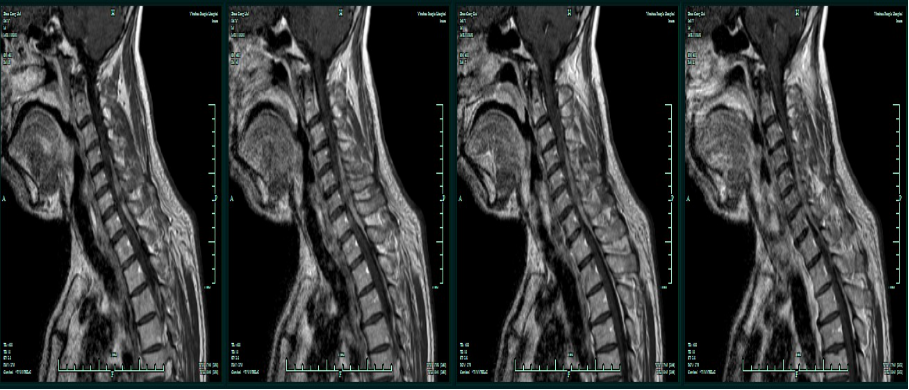

MRI增强:C4-T1椎管内髓外占位,淋巴瘤可能性大。

术前T1增强

T1增强轴位